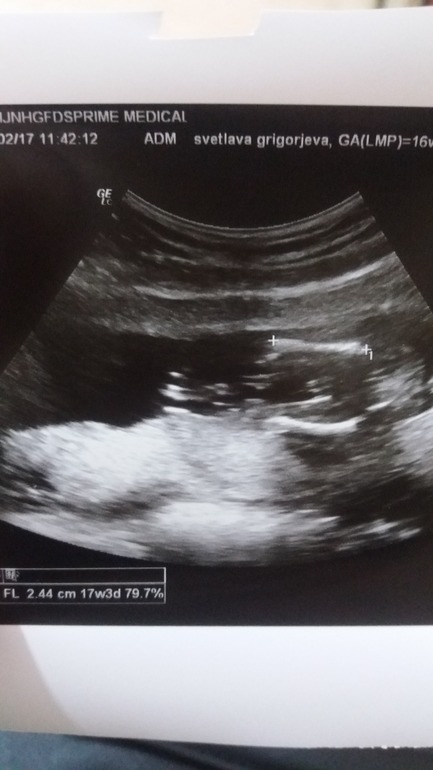

УЗИ, КТГ, доплерДевочки, помогите разъяснить, кто у нас мальчик или девочка?

Девочки, помогите разъяснить, кто у нас мальчик или девочка?